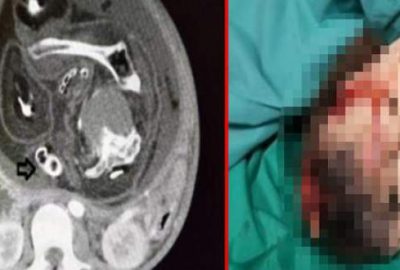

Midesi bulanıyordu! Karnından ikiz kardeşi çıktı…